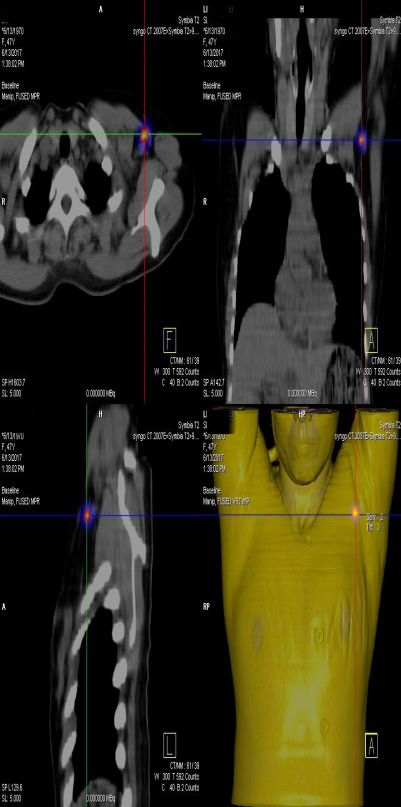

前哨淋巴結(jié)顯像技術(shù)一般在腫瘤附近注射放射性核素標(biāo)記特殊藥物,這種藥物會(huì)被前哨淋巴結(jié)攝取,存在于前哨淋巴結(jié)中。24小時(shí)之內(nèi)都可用SPECT-CT進(jìn)行前哨淋巴結(jié)顯像檢查。

患者李女士,發(fā)現(xiàn)右側(cè)乳腺腫物,來(lái)我院就診,行乳腺腫物局部擴(kuò)大切除術(shù),術(shù)后病理回報(bào):右乳腺浸潤(rùn)性導(dǎo)管癌III級(jí),伴原位癌。擬行右乳腺癌切除術(shù),提檢前哨淋巴結(jié)顯像檢查,明確有無(wú)淋巴結(jié)轉(zhuǎn)移。